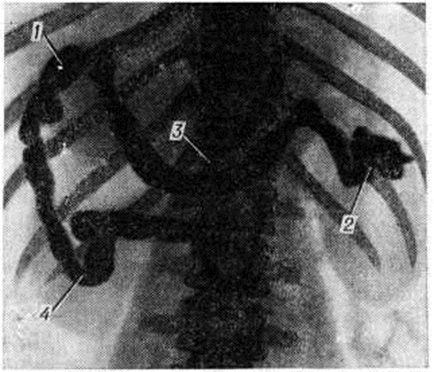

Рис. 5.

Спленопортограмма при внепечёночной портальной гипертензии: отсутствие основного ствола селезёночной вены с множеством вновь образованных сосудов (1); ретроградно заполнившиеся расширенные вены желудка и пищевода (2); стеноз внутрипечёночных ветвей воротной вены и её деформация (3).